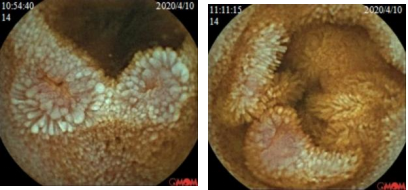

图1 胶囊内镜(胶囊运行4小时23分至12小时1分,可见散在多个片状、横行或纵行糜烂)

转折点: 2020年4月再次因腹胀腹泻就诊于当地医院,完善大便OB阳性,胶囊内镜(胶囊运行4小时23分至12小时1分,可见散在多个片状、横行或纵行糜烂),内镜诊断:1.小肠炎 2.小肠血管显露 3.小肠憩室。入院后予以输血、调节肠道菌群、补铁等对症支持治疗。出院诊断:1.小肠病变性质待定,克罗恩病待排,2.缺铁性贫血,3.胆汁反流性胃炎,4.低蛋白血症。2020年10月,患者因同样原因再次入住当地中医院,查大便OB仍阳性,贫血持续存在。此时,消化科医生首次提出“小肠疾病导致慢性失血”的假设,但仍未跳出“炎症性肠病”的思维定式。